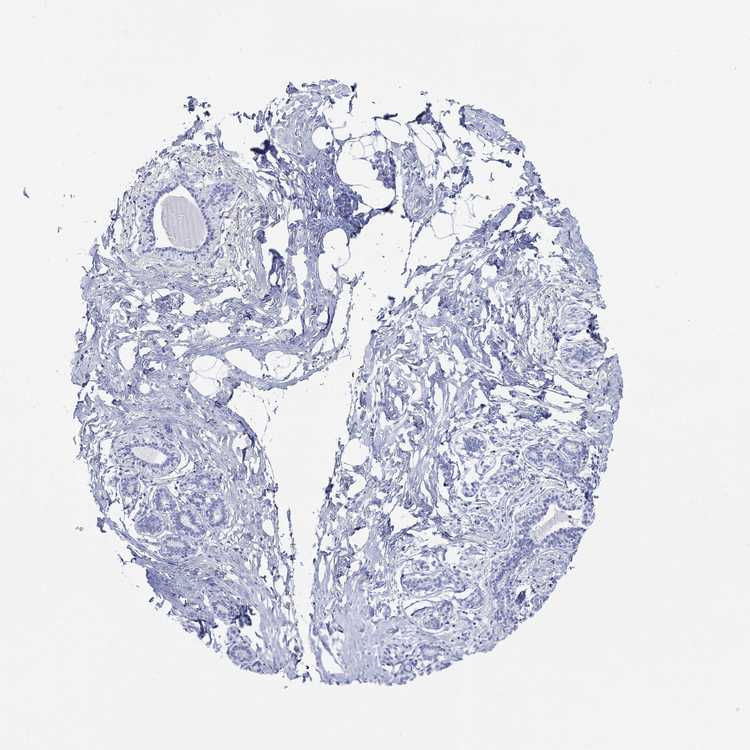

BREAST - Antibody stainingi

Antibody staining in the annotated cell types in the current human tissue is reported as not detected, low, medium, or high, based on conventional immunohistochemistry profiling in selected tissues. This score is based on the combination of the staining intensity and fraction of stained cells.

Each image is clickable and will lead to virtual microscopy that enables deeper exploration of all samples and also displays staining intensity scores, fraction scores and subcellular localization as well as patient and tissue information for each sample.

Antibody HPA061691

Adipocytes Not detected

Glandular cells Not detected

Myoepithelial cells Not detected